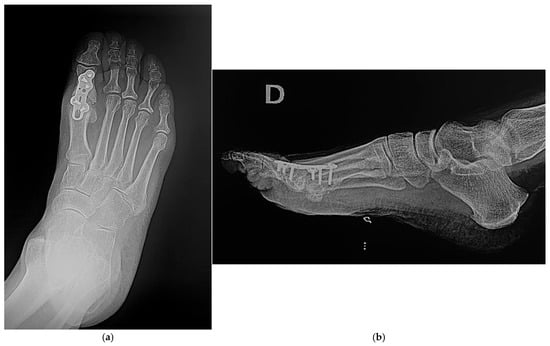

In the WIS group, an interfragmentary headless compression screw, with a diameter of 3.5 mm, was placed across the MTPJ from distal medial to proximal lateral, to achieve interfragmentary and cross-joint compression (Figure 1). The locking plate was then applied dorsally as a neutralization plate. In the WOIS group, interfragmentary compression was achieved through the oval hole in the same locked dorsal plate (Figure 2).

Figure 1. Postoperative X rays in the WIS group in two projections: Anteroposterior (a) and Lateral (b).